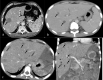

The purpose is to discuss abdominal tuberculosis mimicking malignancy involving the abdominal viscera. TB of the abdominal viscera is common, especially in countries where tuberculosis is endemic and in pockets of non-endemic countries. Diagnosis is challenging as clinical presentations are often non-specific. Tissue sampling may be necessary for definitive diagnosis. Awareness of the early and late disease imaging appearances of abdominal tuberculosis involving the viscera that can mimic malignancy can aid detecting TB, providing a differential diagnosis, assessing extent of spread, guiding biopsy, and evaluating response.